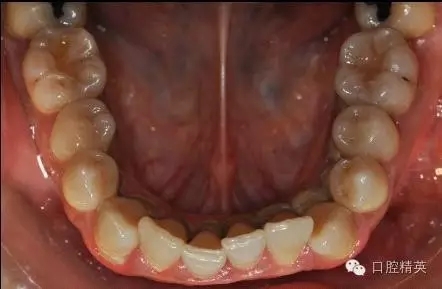

本病例 :女 34歲,主訴刷牙出血,覺牙齒輕度松動一年。

檢查見大量齦上及齦下結(jié)石,探診出血,牙周袋較深,32-42 II度松動。X線片顯示牙槽骨水平吸收。

治療前: